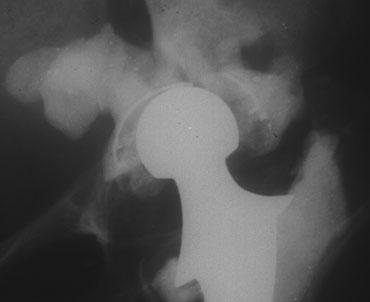

Dislocation

Như đã thảo luận ở trên, trật khớp hoặc bán trật khớp của các thành phần có thể xảy ra do các yếu tố từ phía bệnh nhân bao gồm trương lực cơ kém hoặc chấn thương, hoặc do các yếu tố phẫu thuật như đường tiếp cận phẫu thuật phía sau (thay vì phía bên).

Một yếu tố khác là khó khăn trong việc đạt được góc nghiêng lý tưởng của cấu phần ổ cối. Đây thường là kết quả của những thay đổi thoái hóa nặng hoặc loạn sản.

Trật khớp có thể xảy ra theo hướng ra sau, ra trước hoặc ra bên.

Ở bên trái là một trường hợp khác với tình trạng trật khớp do hậu quả của việc nghiêng chỏm do lỏng khớp.